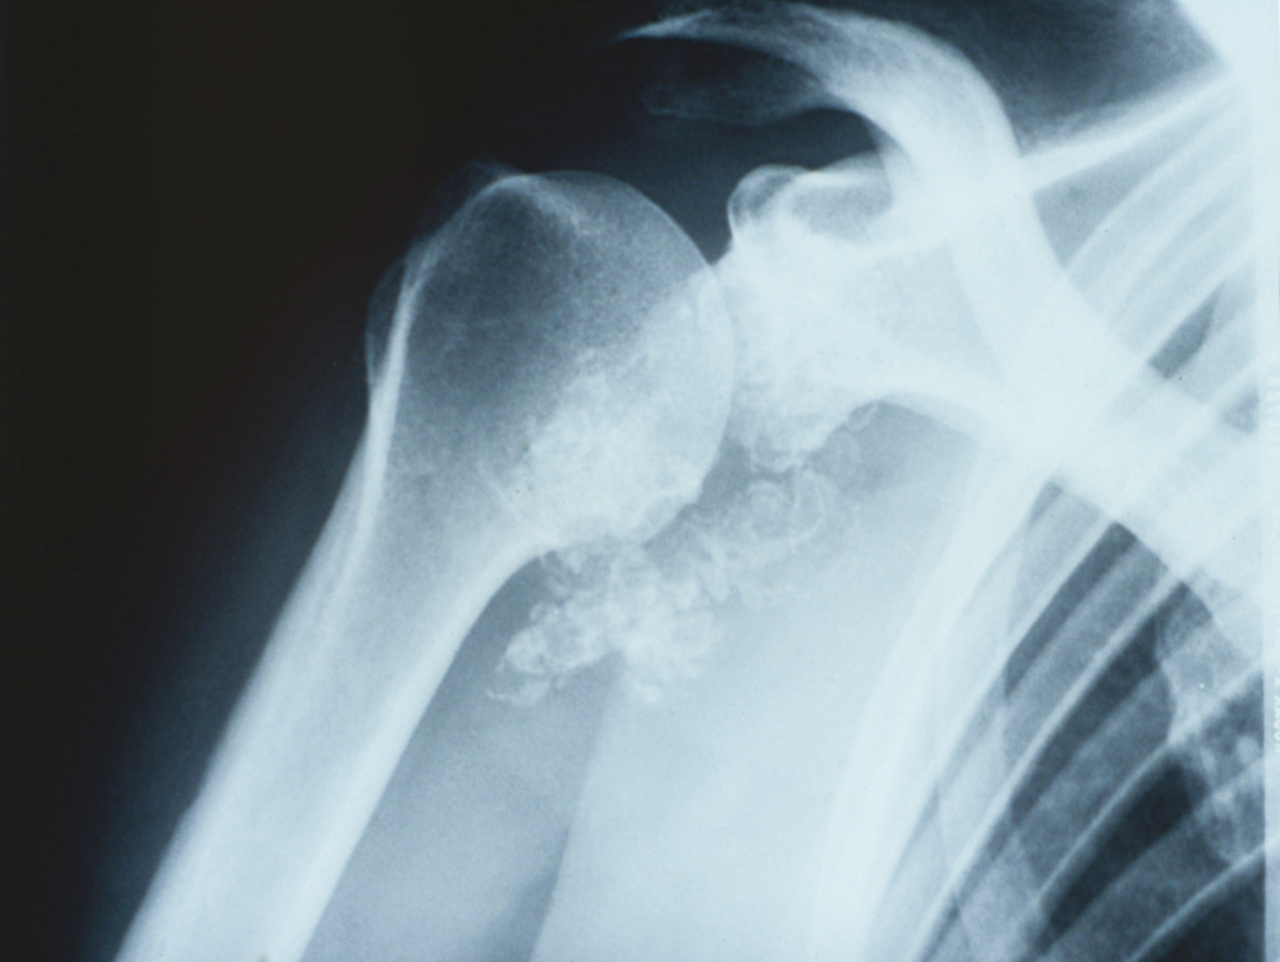

Quel est votre diagnostic ?

Il s'agit de l'aspect radiographique d'une chondromatose synoviale. La chondromatose synoviale est une métaplasie chondroïde, rare, de la membrane synoviale d'étiologie inconnue. Elle se caractérise par la formation de petits corps cartilagineux (chondromes) ou ostéocartilagineux dans les articulations, les bourses séreuses ou la gaine synoviale, qui, en se détachant, constituent des corps étrangers intra-articulaires. La gêne douloureuse est plus ou moins importante, les localisations préférentielles sont le genou, la hanche, le coude ou l'épaule. Le début est insidieux et peu invalidant expliquant le retard thérapeutique. L'évolution spontanée se fait vers l'arthrose, d'où l'intérêt d'intervenir avant que des lésions importantes ne s'installent mettant en péril l'articulation.